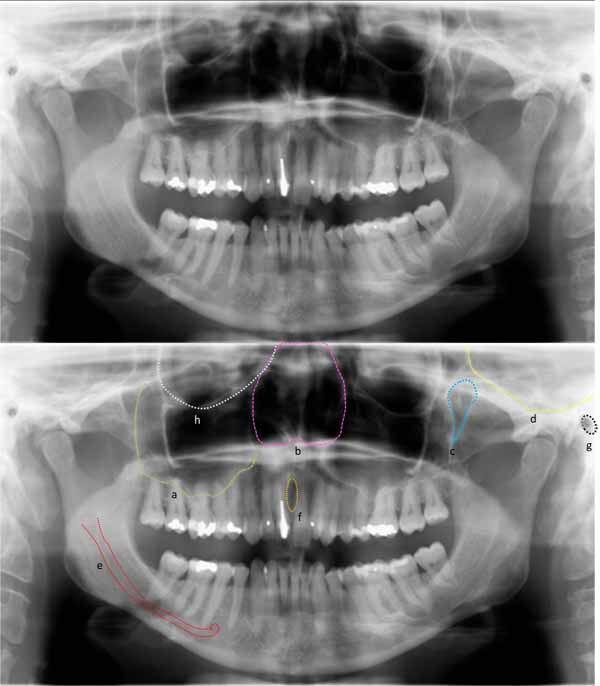

歯科X線写真における正常な解剖学_図26